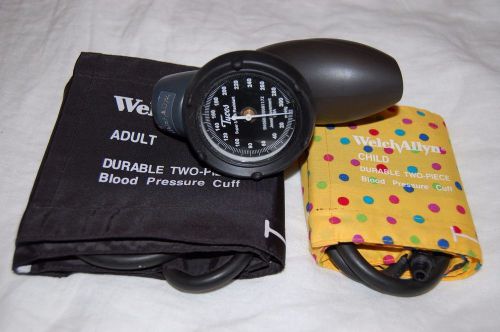

Welch Allyn Sphygmomanometer Model DS58